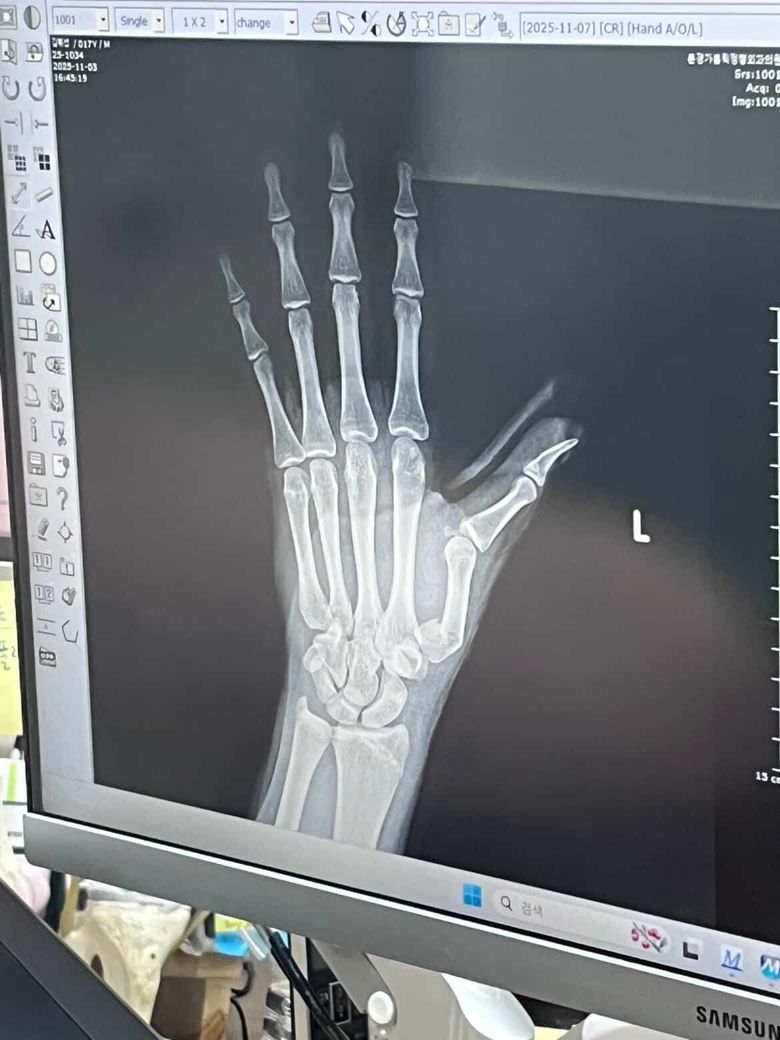

핀수술후 단차?재수술여부.휴유증

수술전 간단한수술이라고 걱정말라고하시더니 끝나고나서90%잘됐다.100%까지할려면 피부절개해서 해야하는데 이정도면 잘됐다고 하셔서 안심하고 있었는데 3일뒤 사진을보니 단차도 그대로인것같고 주변에서 재수술 권하고있는데 꼭해야하나요?향후 후유증이생길까요?고등학생이라 오래 입원할수있는상황도아니고 전신마취안하면 두번다시 안한다고 하고있습니다.

• 1번 째 사진

• 2번 째 사진